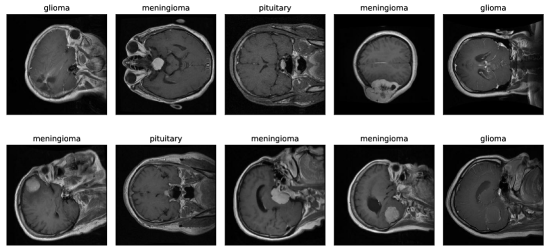

The dataset [19] contains 3064 T1-weighted contrast-enhanced images of the brains of 233 patients who had been diagnosed with one of three types of brain tumours: meningioma (708 slices), glioma (1426 slices), or pituitary tumour (930 slices). The information can be downloaded in the form of Matlab files (.mat files). Each image file includes a struct that contains pertinent information about the image, such as the label (1 for meningioma, 2 for glioma, and 3 for pituitary tumour), patient ID (PID), image data, and tumour Border. The tumor border is a vector that contains the coordinates of distinct points on the tumor’s edge, and it is obtained by manually tracing the tumor border. Due to the availability of this information, the generation of a binary image of the tumor mask is made simple. In addition, the dataset contains a tumor Mask, which is a binary image with the tumor region represented by a string of ones.

The distribution of the dataset is depicted in Fig. 4

Figure 4: The distribution of brain tumor dataset

The preprocessed images are sharper, brighter, and have more detectable details than the original images, making them appropriate for driving into the model and achieving greater performance than existing works. Figure 5 illustrates the image preprocessing steps for brain tumor types, including glioma, meningioma, and pituitary. The top section of the figure (a,b,c) shows the images before preprocessing, while the bottom section (d,e,f) displays the images after the preprocessing steps have been applied.

Figure 5: Brain glioma, meningioma and pituitary image before and after image preprocessing

We have further enhanced the experimental setup by incorporating additional photographs to measure the impact of the image preprocessing techniques proposed in this paper. In Figure 6a and 6b, we present a selection of before-and-after images randomly selected from our dataset, illustrating the demonstrable effects of the image processing methods employed. These visual examples serve to provide compelling evidence of the efficacy of our image preprocessing approach, enhancing the attractiveness and visual appeal of our research

(a) Before Image Preprocessing

(b) After Image Preprocessing

Figure 6: Sample of before and after image preprocessing